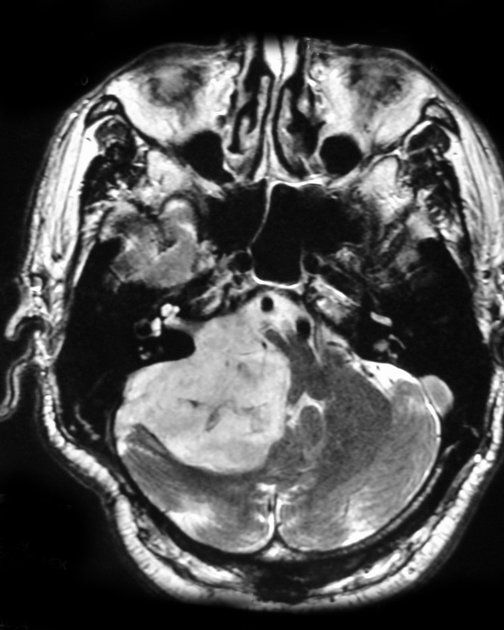

This article focuses on the multifaceted and deeply challenging aspect of modern oncology: the treatment of malignant gliomas, particularly glioblastoma. It unravels how the tumor’s microenvironment, cellular adaptability, and intricate interactions with immune cells and the brain itself make therapy not only difficult but elusive. Rather than proposing a single silver bullet, it examines a layered treatment model targeting several dynamic “hallmarks” of cancer through repurposed drugs, immunotherapies, and precision strategies tailored to each patient.

But as this complex puzzle unfolds with aggressive tumors, stealthy stem-like cells, and a battlefield of immune evasion, one can’t help but ask: what if the very brain that harbors the tumor holds the key to its destruction?